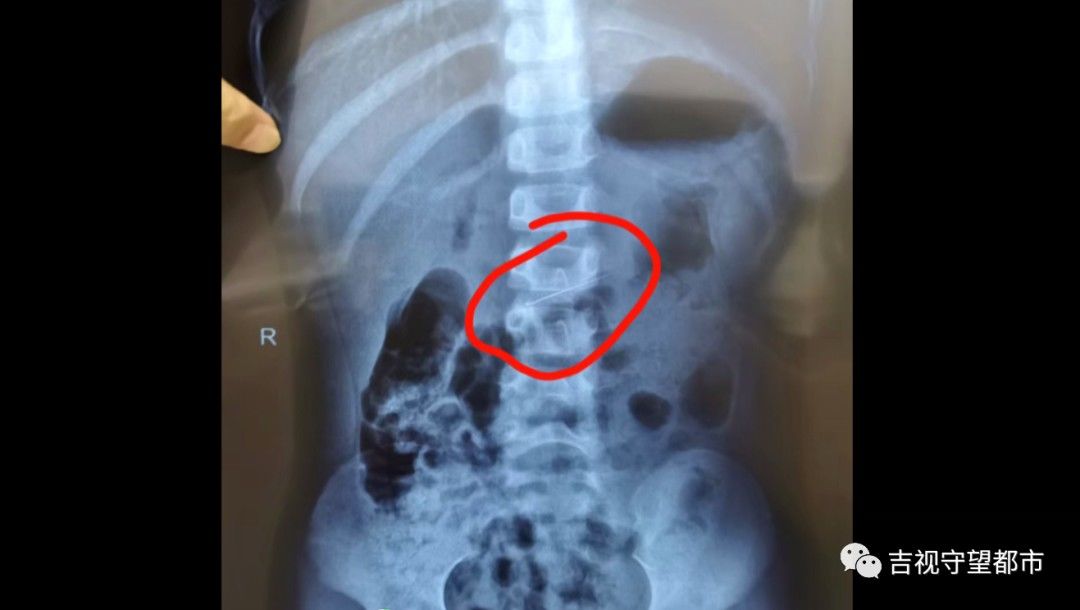

据家属描述,孩子误吞的这根修牙针长约4厘米,又细又尖,情况紧急,医生马上为患儿做了鼻咽镜,结果并未发现修牙针,怀疑针已经进入到消化系统。随即,院方马上为患儿安排拍片,最终在胃里发现了修牙针。